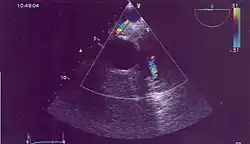

- serca – w połączeniu z echem serca ultrasonografia dopplerowska jest nieoceniona przy wykrywaniu wad zastawkowych